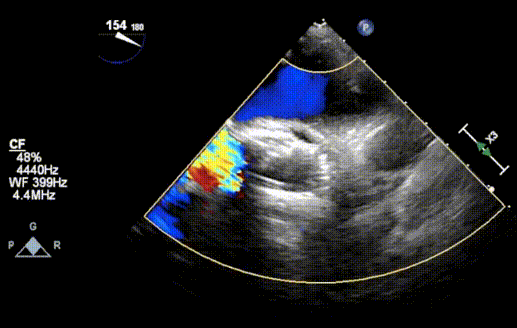

超声

• 男性,65岁;

• Type0 二叶式主动脉瓣,重度狭窄(Vmax:5.54m/s,平均压差:79mmHg,瓣口面积:0.43cm²);

• 左心房增大,左室壁增厚;

• 二尖瓣、三尖瓣反流(轻微);

• 左室壁节段性运动异常;

• 左室收缩功能正常低值(EF:54% ,EDV:83ml)。

超声评估